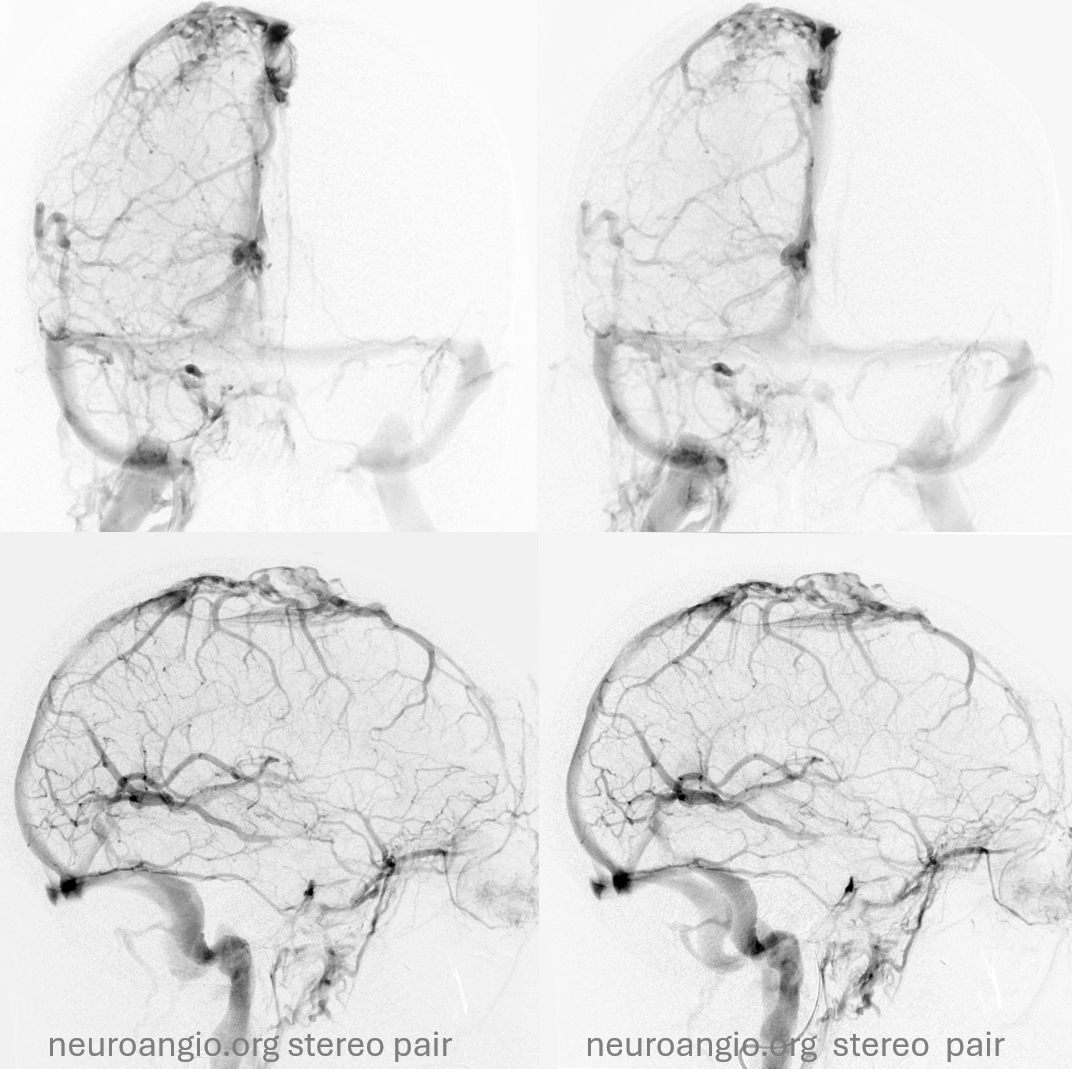

Later on… right side is good

Left side is bad — can you see it?

Later phase of bad